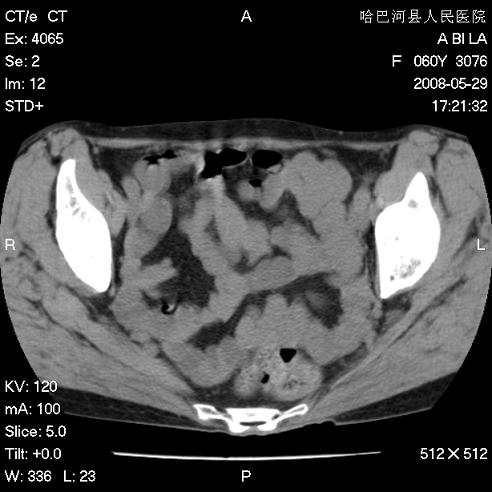

标题: CT13730:排尿不畅4天,抗炎治疗无效,现尿中可见血块 [打印本页]

标题: CT13730:排尿不畅4天,抗炎治疗无效,现尿中可见血块

手术结果及病理:膀胱癌并膀胱壁转移,膀胱内血块